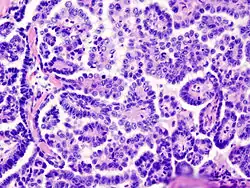

| Medium power slide of ovarian serous adenocarcinoma stained using haematoxylin and eosin | |

Papillary serous cystadenocarcinomas may exhibit psammoma bodies upon histopathology.[3]